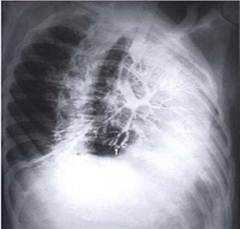

Отклонение от нормы

При бронхографии можно выявить бронхоэктазы или обструкцию бронха опухолью, каверной или инородным телом. Необходимо соотнесение полученных данных с анамнезом, результатами физикального обследования, а также других пульмонологических исследований.

Как оценивают патологические образования?

При обнаружении на снимках патологического образования, врач руководствуется стандартной схемой его оценки:

- положение по отношению к долям легкого, бронхам, ребрам и позвонкам;

- количество образований;

- форма: округлая, овальная, неправильная;

- размеры: обычно измеряют наибольший и наименьший диаметр (в случае со стенозом - ширину и протяженность);

- интенсивность тени на рентгенограмме позволяет судить о плотности патологического образования;

- рисунок: образование может быть однородным или иметь внутри какую-то структуру;

- контуры: четкие или нечеткие;

- границы: ровные или не ровные;

- смещение: меняет ли образование свое положение в процессе дыхания?